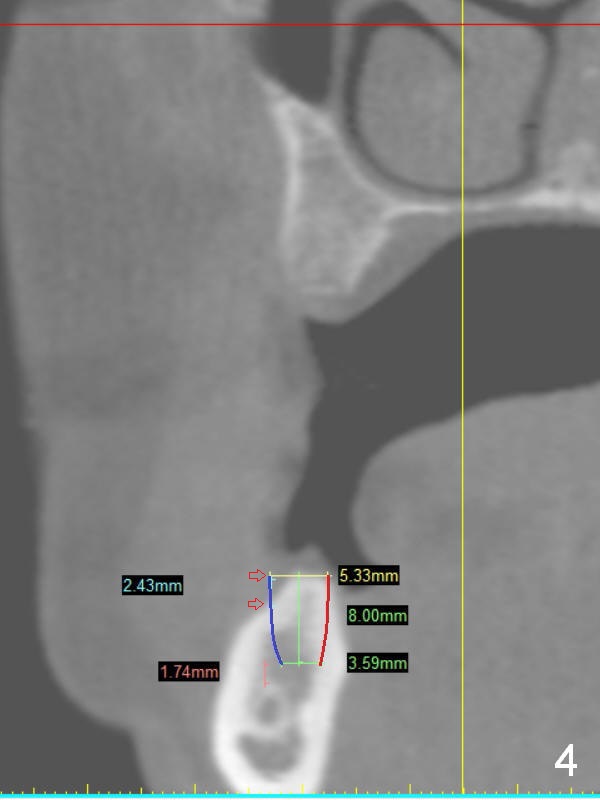

A 49-year-old lady is petit. An implant is placed at #3 and ready for restoration. The crest at #30 is narrow (Fig.1 ^). Bone density at the cortex, around the Inferior Alveolar Canal (IAC) and the medulla is D1, D2 and D3, respectively. It appears that a 10 mm bone-level implant is too close to IAC (Fig.2), whereas a 8 mm one has enough clearance (Fig.3,4). With the same diameter, there will be less thread exposure if the implant is placed a little lingually (Fig.4 (between arrows), as compared to Fig.3).